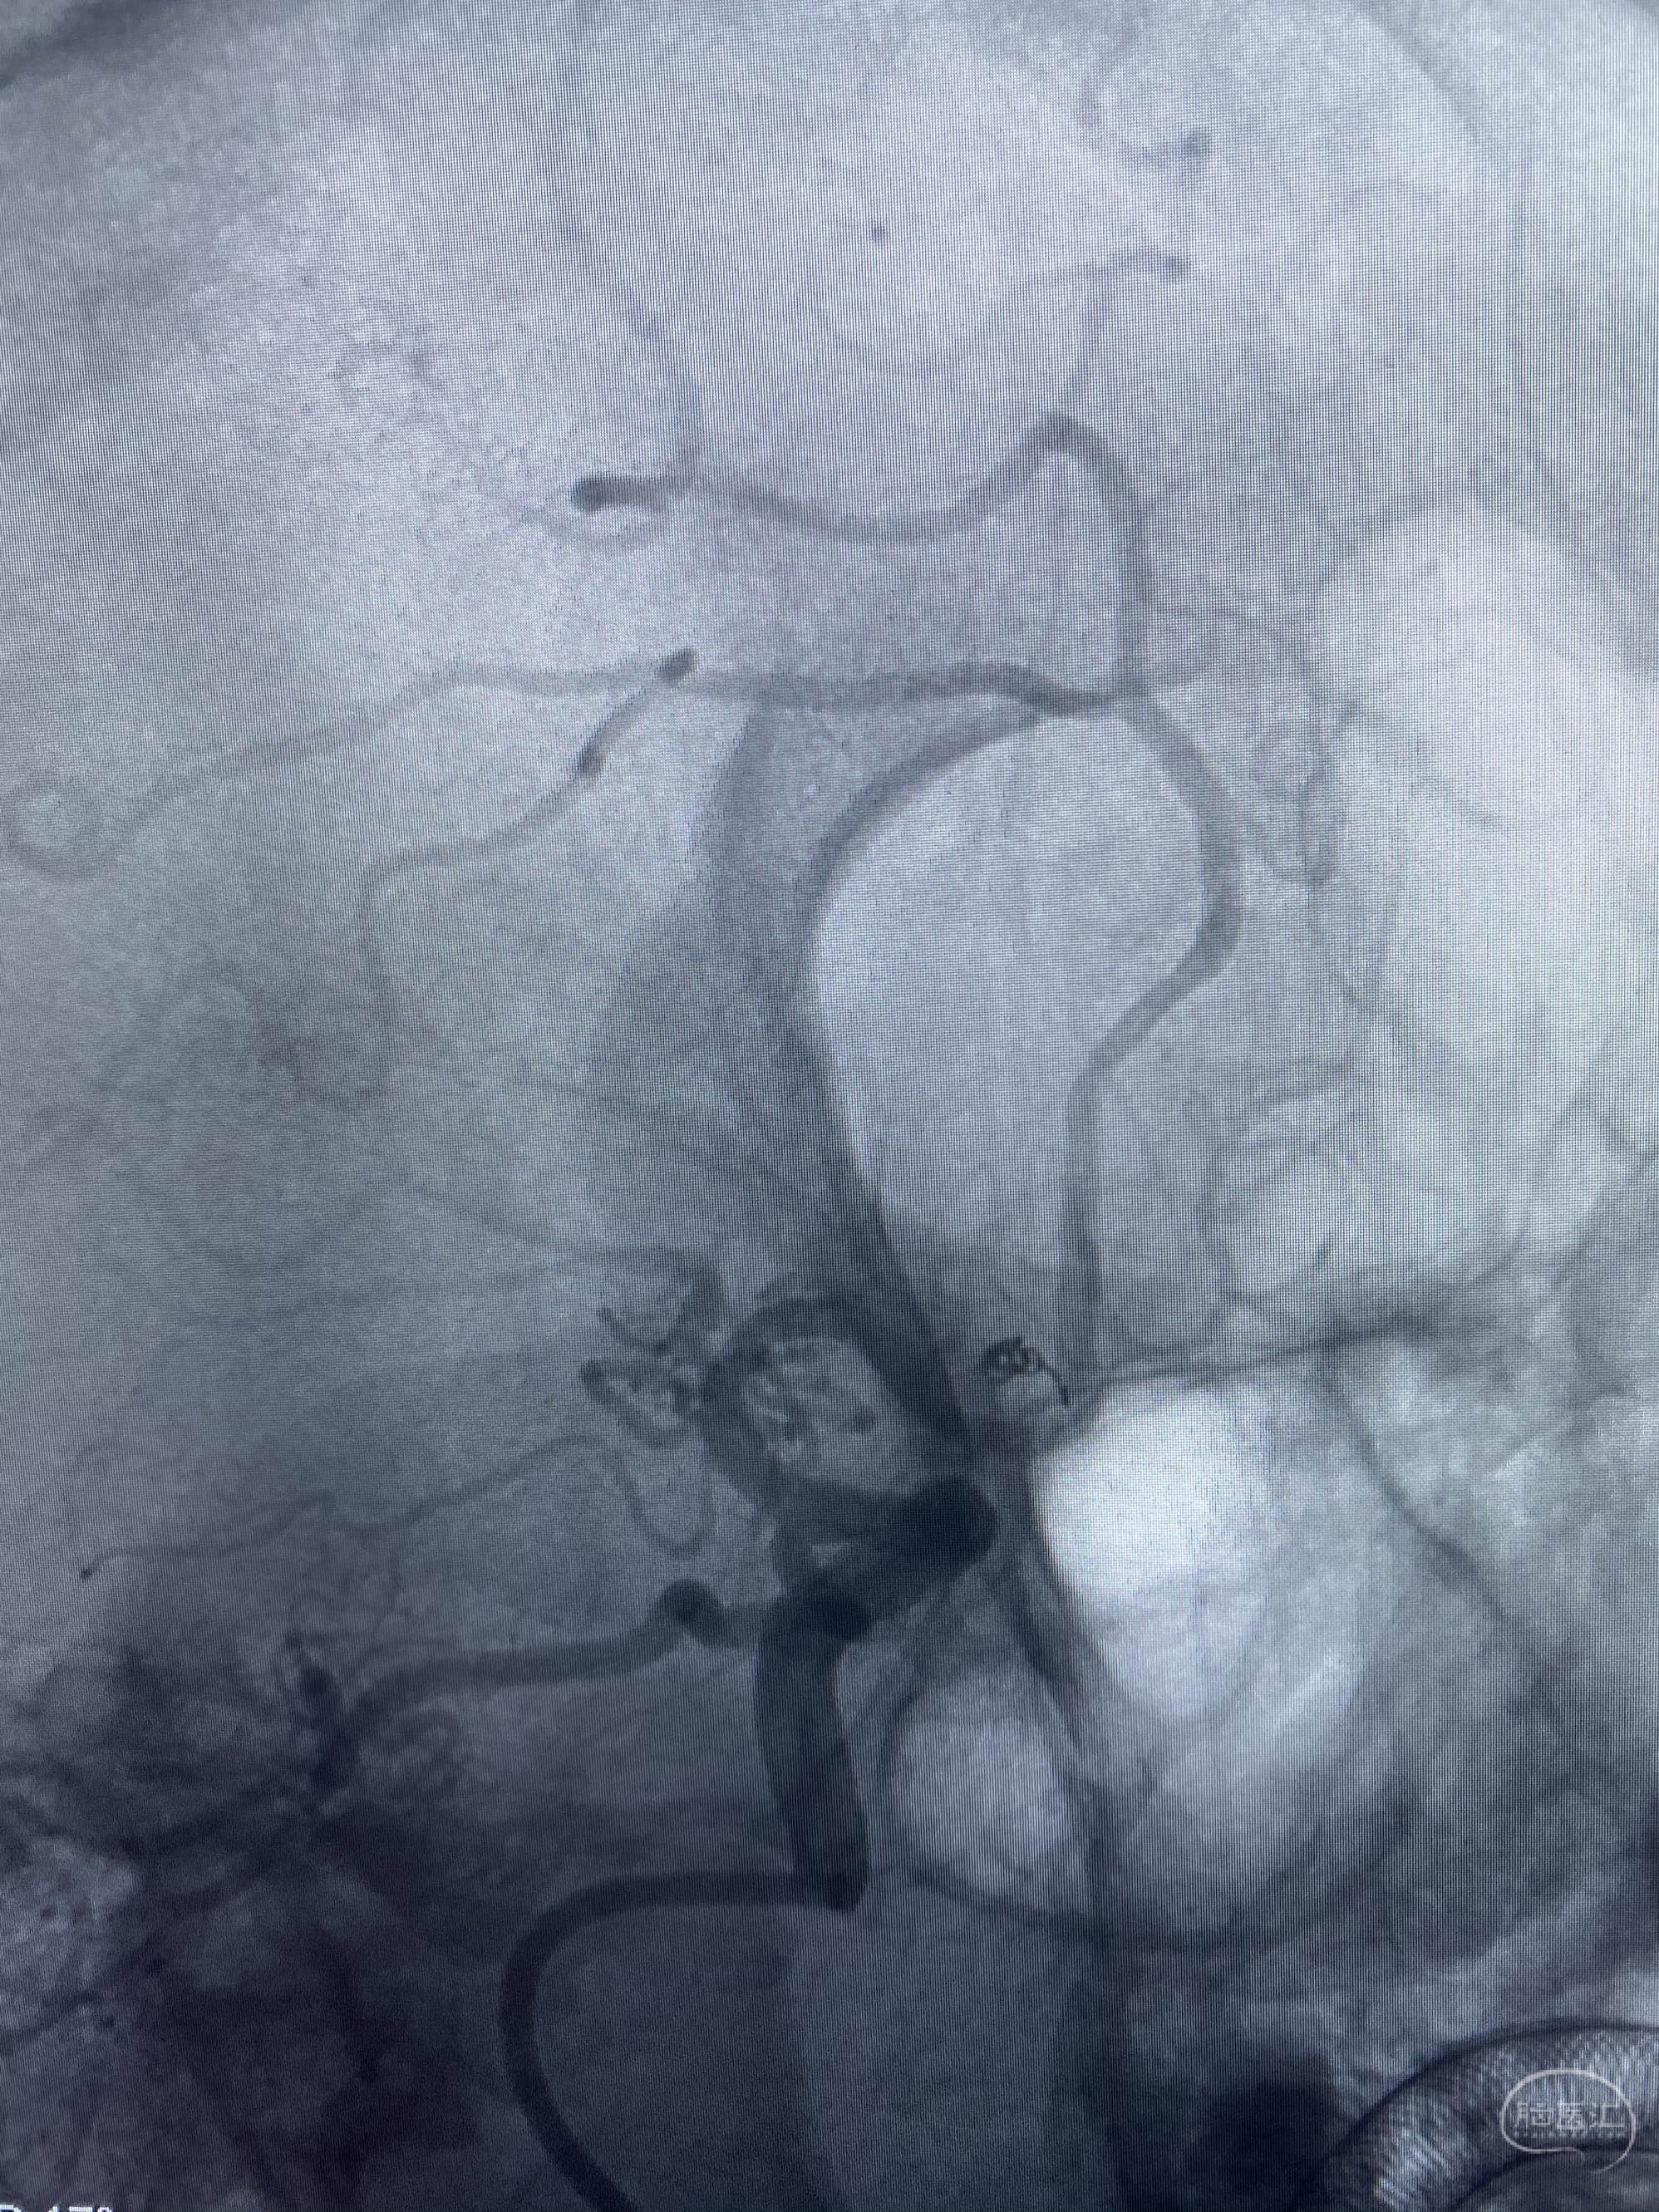

MLS,M79Y,sah,双侧MCA烟雾病,Heubner返动脉瘤,前交通段开窗,细支发出Heubner返动脉,瘤颈细长,瘤颈口比微导管细,弹簧圈2mmx3cm“隔山打牛”填塞治愈,Heubner返动脉保留。

该患者术后2天观察神志清楚,四肢活动正常。

Heubner返动脉是由大脑前动脉A1末端发出的豆纹动脉,由于走形和A1段相反,故称Heubner返动脉,该动脉梗塞可能引起尾状核头梗塞,引起偏瘫和面瘫,便身震颤等症状。